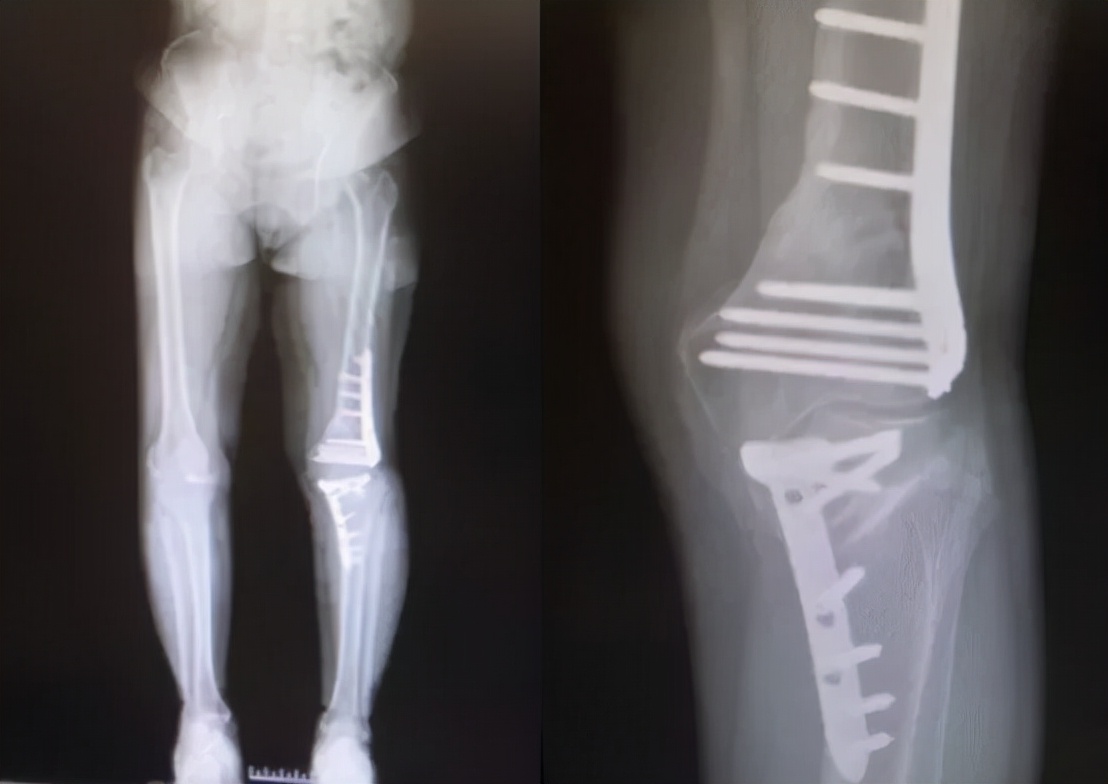

入院后刘万军主任对赵女士进行了详细的检查发现,赵女士的左膝关节存在严重的内翻畸形,关节间隙明显缩小。不仅股骨侧存在畸形,且胫骨侧也存在畸形。当股骨和胫骨均存在畸形时,试图仅通过胫骨侧截骨或股骨侧截骨来矫正这类畸形可能会导致术后关节线发生非生理性倾斜,使得关节表面软骨遭受的剪切力增加。长期的剪切应力会使得软骨超过其承载负荷的极限,造成软骨面的损伤,加快骨关节炎的发生和进展。此外,关节线倾斜还可能引起膝关节周围韧带的松弛,从而在负重时容易产生半脱位。因此,刘万军主任团队准备对赵女士的左膝关节同时进行股骨远端截骨术+胫骨高位截骨术(DFO+HTO),以此矫正左膝严重内翻畸形,更好地恢复关节力线和膝关节的正常解剖角度。

通过术前在计算机上精确规划截骨线及矫正角度后,刘万军主任团队对赵女士的左膝同时进行了股骨远端截骨术+胫骨高位截骨术。先取左膝关节的正中切口,行内松解后,按标准手术行髌骨修整。股骨切骨完整后,试装假体复位,调试后用骨水密固定安装假体。之后取左膝关节屈膝90度,采用外侧倒T行切口,分离胫骨外侧组织,在胫骨平台远侧2cm处截骨,用C形臂X线机检查位置,反复检查下肢对线,在腓骨前方行内固定。手术进行的非常顺利,出血少,历时约3小时10分钟。术后赵女士的膝关节疼痛消失,膝内翻畸形得到明显改善。

术前